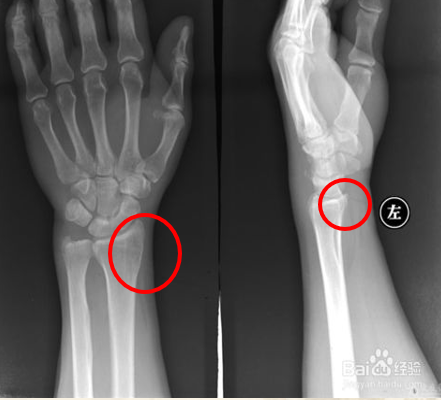

X线检查X片可见肌腱及其腱鞘有钙质沉积。也有助于本病的诊断。

桡骨茎突狭窄性腱鞘炎 X线片